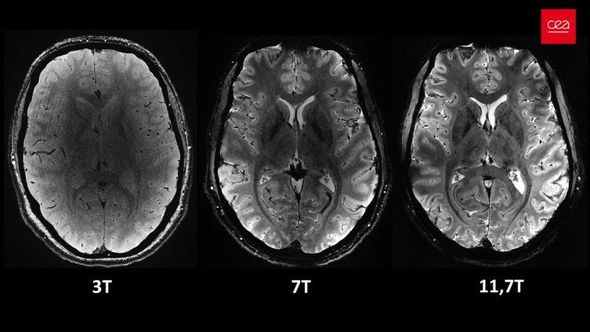

Açıqlamada qeyd olunub ki, 11,7 Tesla maqnit gücünə malik “Iseult” cihazı ilə qısa müddətdə çəkilən görüntüləri xəstəxanalarda istifadə edilən cihazlarla əldə etmək saatlar çəkə bilər.